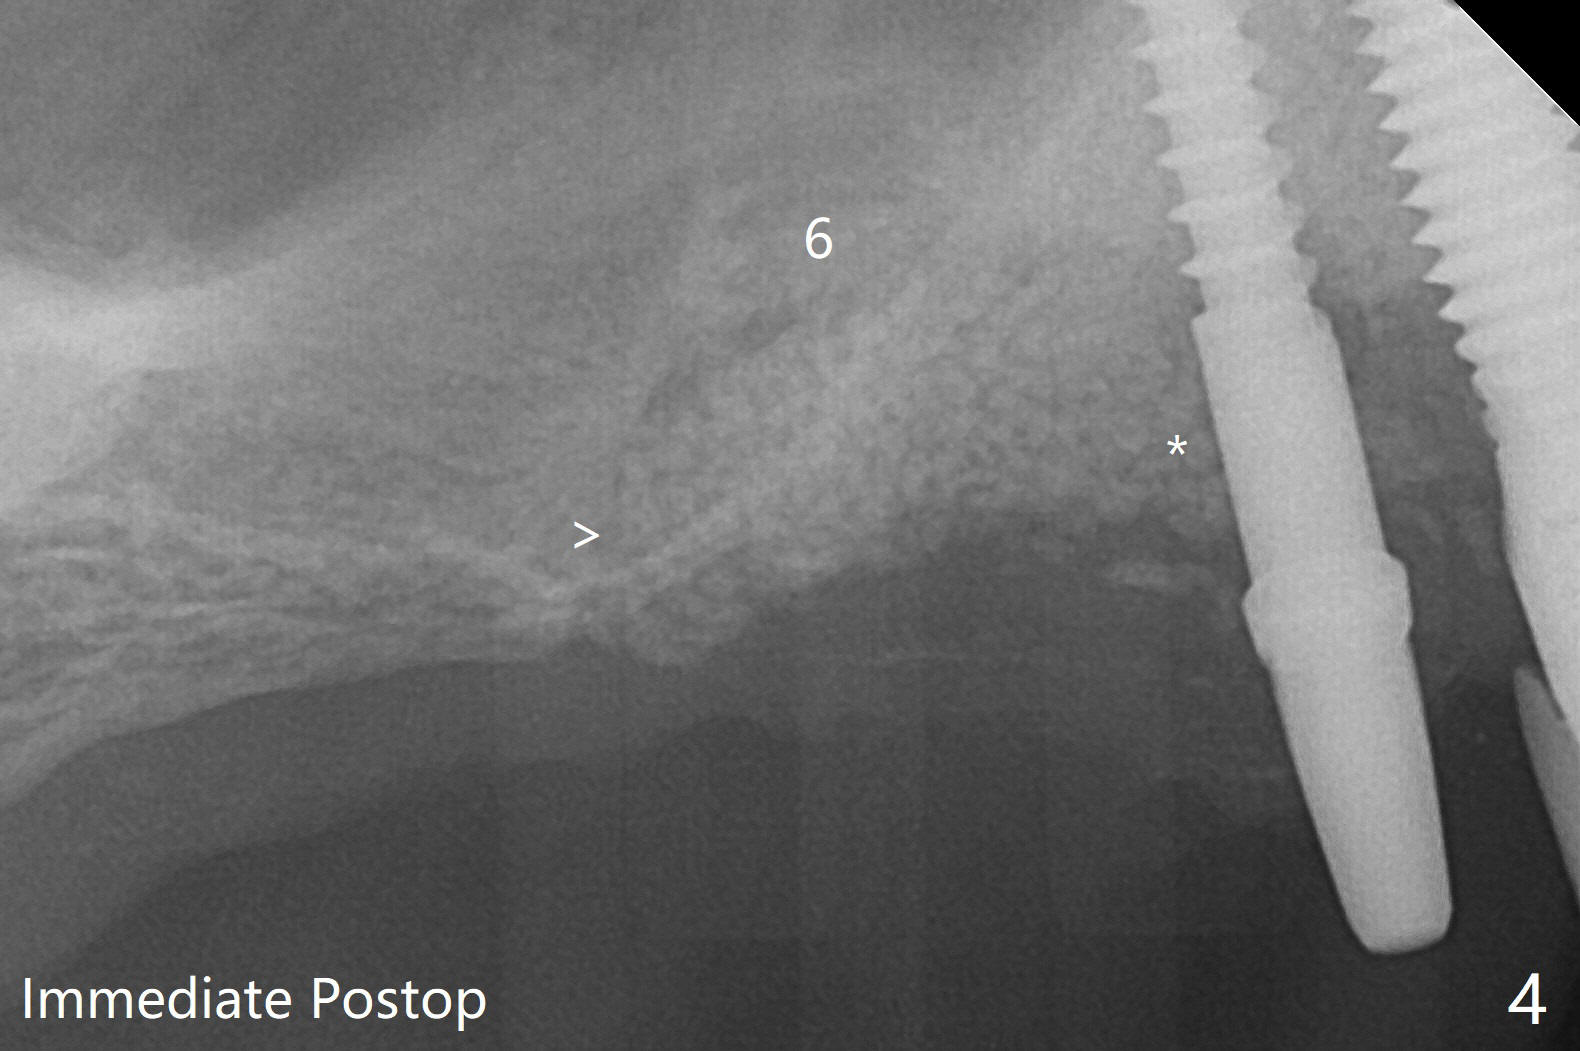

术前检查发现右上6颊侧牙龈沟有脓性分泌物(图一),翻瓣显示骨质吸收(图二),曾经植骨三次,只好去骨,取出植体,远中颊侧轻度上颌窦穿孔(图三:>),塞入小块PRF膜后,患处放置粘性骨粉,覆盖两块PRF膜和一片GEM Cap(9-12月吸收膜),三者近中一端有一个洞,挂在5基台上固定。术后即刻根尖片显示骨粉充填穿孔(图四:>),6缺失区以及5远中(*)。术后第二天牙周敷料脱落,术后16天病人回来,要求剪除缝线,伤口尚未关闭,下面黄色骨粉好像挺牢靠;为了减少继续骨粉丧失,使用树脂敷料(图五)。术后四周敷料稳定,牙龈健康,但是不放心下面伤口愈合,暂时没有撤去敷料。术后四个月骨质高度不足(图六至八),上颌窦膜薄,提升不容易,可放置5x7.3毫米植体(IBS),PRF。Return to No Caries 4 Placement 种植杂谈 Xin Wei, DDS, PhD, MS 1st edition 01/26/2021, last revision 07/30/2021